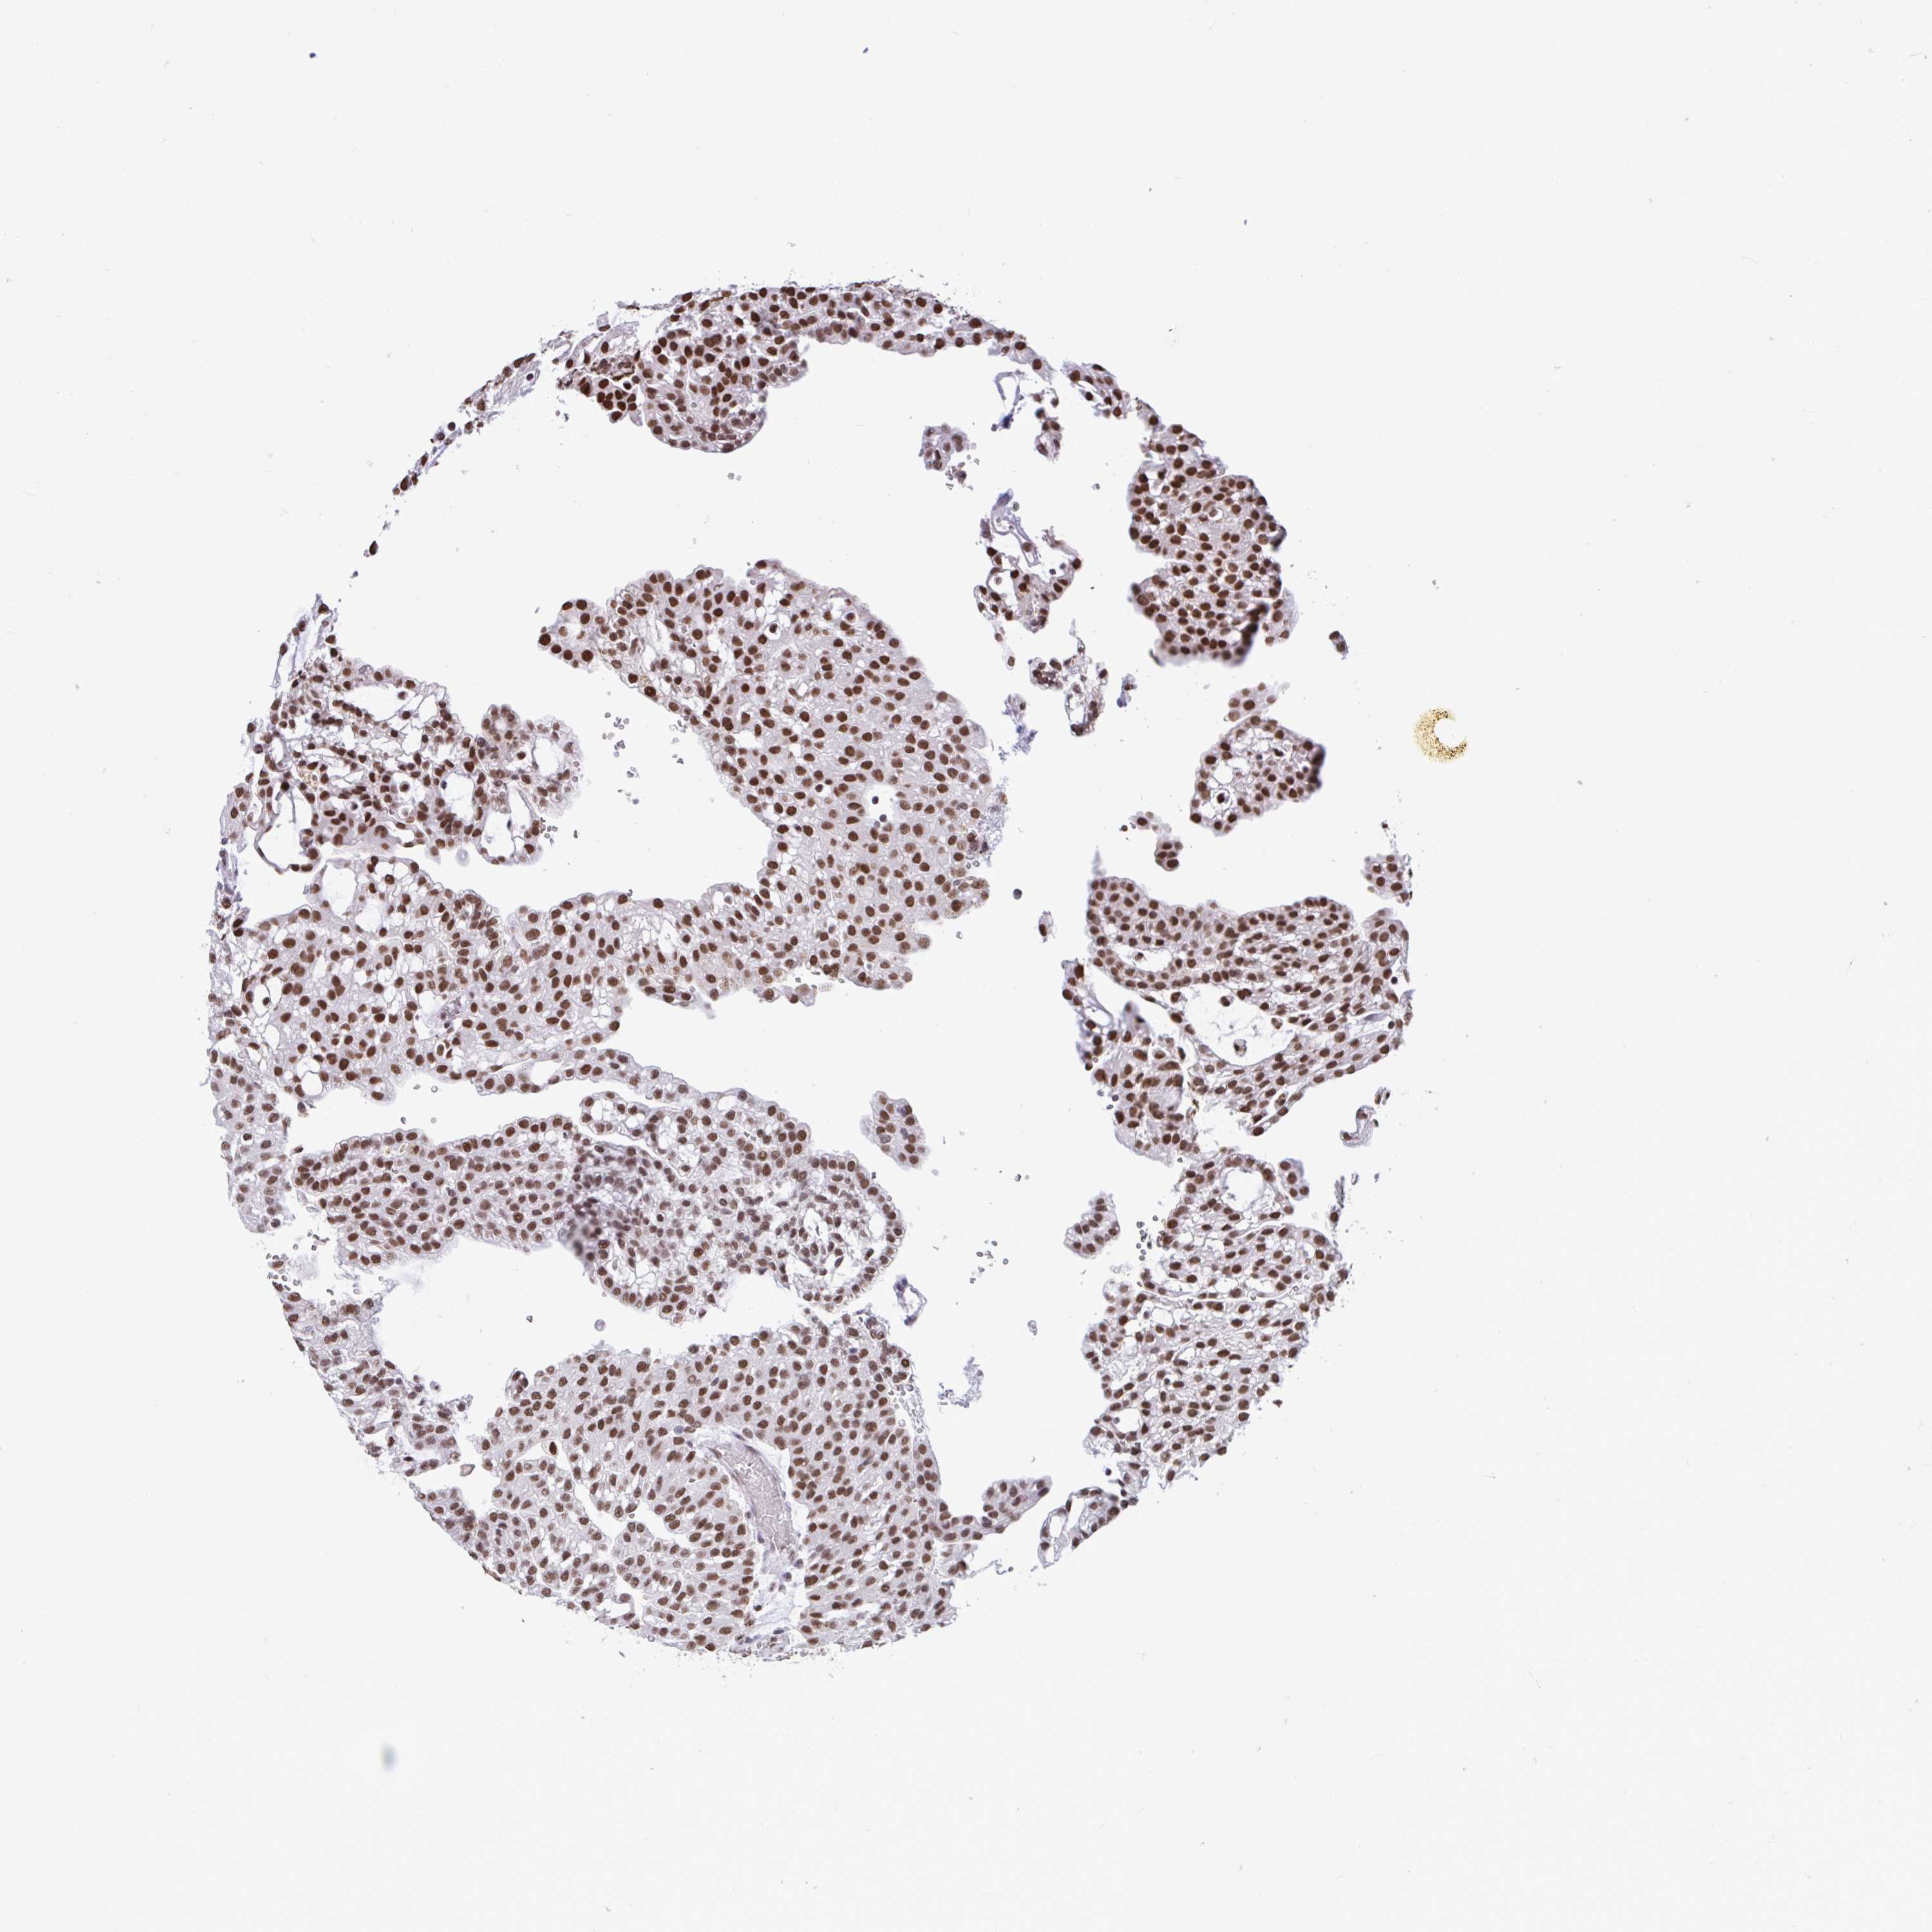

KIDNEY RENAL PAPILLARY CELL CARCINOMA (TCGA) - Interactive survival scatter ploti

The Survival Scatter plot shows the clinical status (i.e. dead or alive) for all individuals in the patient cohort, based on the same data that underlies the corresponding Kaplan-Meier plots. Patients that are alive at last time for follow-up are shown in blue and patients who have died during the study are shown in red.

The x-axis shows the expression levels (FPKM) of the investigated gene in the tumor tissue at the time of diagnosis. The y-axis shows the follow-up time after diagnosis (years). Both axes are complimented with kernel density curves demonstrating the data density over the axes. The top density plot shows the expression levels (FPKM) distribution among dead (red) and alive patients (blue). The right density plot shows the data density of the survived years of dead patients with high and low expression levels respectively, stratified using the cutoff indicated by the vertical dashed line through the Survival Scatter plot. This cutoff is automatically defined based on the FPKM cutoff that minimizes the p-score. The cutoff can be changed by dragging the vertical line or by entering a cutoff value in the square labeled "Current cut-off".

Under the Survival Scatter plot the p-score landscape (black curve; left axis) is shown together with dead median separation (red curve; right axis). Dead median separation is the difference in median mRNA expression between patients who have died with high and low expression, respectively. It is calculated as follows: median FPKM expression of dead patients with high expression - median FPKM expression of dead patients with low expression. This is intended to aid the user in visually exploring custom cutoffs and the associated p-scores and dead median separation.

Individual patient data is displayed and can be filtered by clicking on one or more of the category buttons on the top of the page. Categories describing expression level and patient information include: high, low, alive, dead, female, male and tumor stages. The scale of the x-axis can be toggled between linear and log-scale by clicking on the "x log" button. Mouse-over function shows TCGA ID, patient information and mRNA expression (FPKM) for each patient.

& Survival analysisi